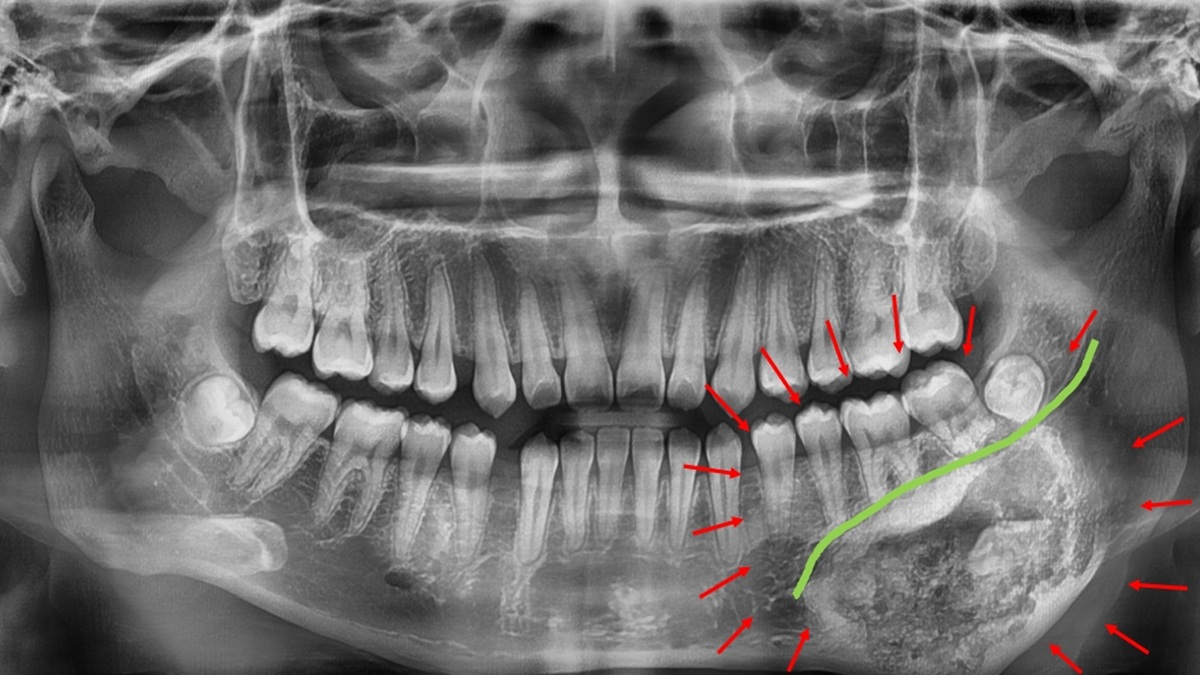

▲經影像與病理切片檢查後,確診為罕見的良性齒源性腫瘤–牙骨質骨化纖維瘤。(圖/記者蕭麗鳳攝)

林楠瑾醫師說,牙骨質骨化纖維瘤的邊界常與正常骨質交錯,若手術切除不夠精準,可能傷及下顎齒槽神經或造成顎骨變形。為提高手術安全與精準度,術前以3D列印技術製作出患者顎骨立體模型,模擬腫瘤切除範圍與骨骼重建角度。透過3D列印手術導引版輔助,醫師得以清楚辨識神經走向與腫瘤邊界,規劃最理想的手術路徑,在完整切除腫瘤的同時成功保留下顎齒槽神經,維持下唇感覺與口腔功能。

▲林楠瑾醫師說,牙骨質骨化纖維瘤的邊界常與正常骨質交錯,若手術切除不夠精準,可能傷及下顎齒槽神經或造成顎骨變形。(圖/記者蕭麗鳳攝)